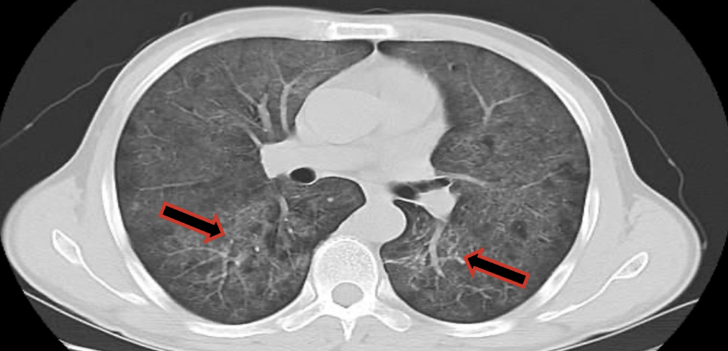

影像学检查:

肺部CT检查报告:检查结果两肺广泛磨玻璃密度灶,建议临床进一步检查除外卡氏肺孢子菌肺炎(图5、图6)。需鉴别诊断:1.大叶性肺炎:胸部CT可见大片的炎症浸润阴影或实变影,其内可见支气管充气征明显,该患者胸部CT可予以排除。2.支气管扩张:表现为慢性咳嗽、大量脓痰、反复咯血、反复肺部感染,查体常有肺部固定性粗湿罗音。胸部片显示肺纹理粗乱或呈卷发状,高分辨CT可见支气管扩张改变。此患者以白痰为主,无咯血,影像学上亦无支气管扩张征象,支气管扩张可除外。

2. 影像悖论:CT示双肺弥漫性磨玻璃影伴小叶间隔增厚,却无胸腔积液或结节,符合“肺泡内泡沫样渗出物蓄积”病理特点。